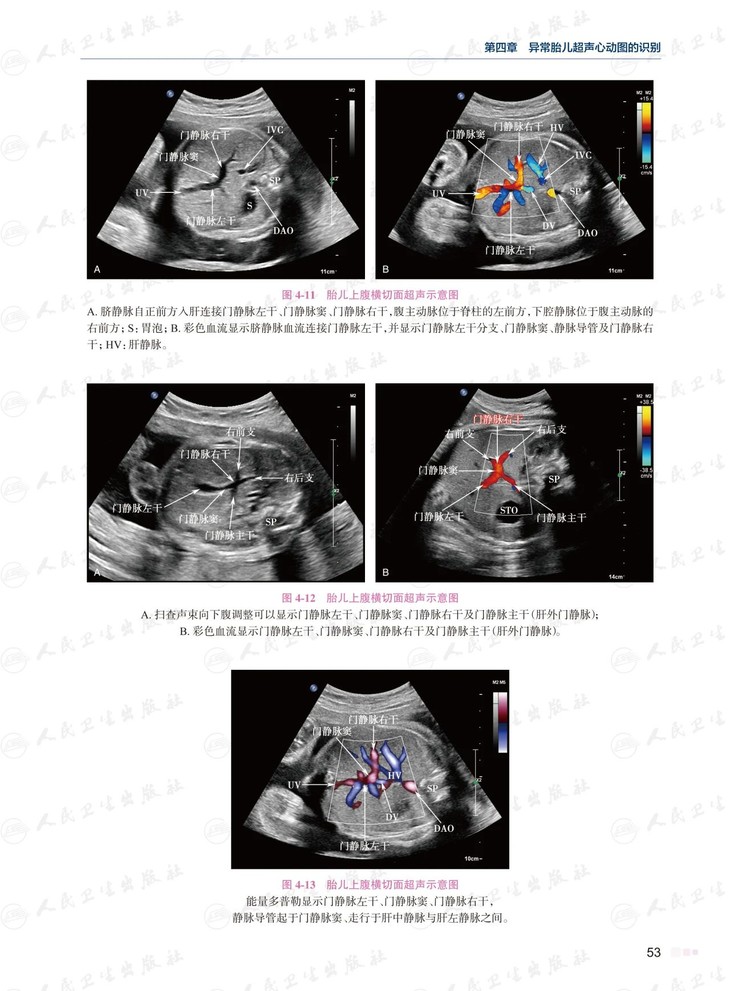

全书共48章,与第1版相比,新版对所有章节内容进行了全面充实和提高,增加了13个新章节;对50余种胎儿先天性心脏病的超声诊断与鉴别做了梳理总结。图文并茂、通俗易懂,并融入作者多年来的诊断经验,对胎儿先天性心脏病的病理生理及超声心动图诊断进行精炼的阐述。每个病种均插入符合胎儿期心脏结构及血流动力学异常的彩色示意图、解剖图、二维超声图及彩色多普勒血流图1700余幅静态图片,1300余幅动态视频图像,几乎所有静态超声图片均附有动态视频图像,使读者能够更好地从复杂心脏畸形解剖、病理生理过渡至胎儿超声心动图诊断,熟悉掌握胎儿先天性心脏病超声诊断技术。